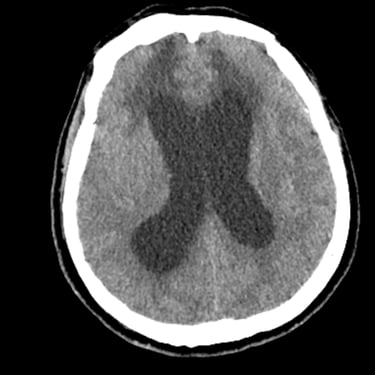

Hidrocefalia – Colocación de derivación ventriculoperitoneal (DVP).

La hidrocefalia es una condición neurológica causada por la acumulación anormal de líquido cefalorraquídeo dentro de los ventrículos cerebrales, lo que genera aumento de la presión intracraneal y deterioro neurológico progresivo. La colocación de una derivación ventrículoperitoneal (DVP) es el tratamiento quirúrgico más utilizado para controlar esta patología. Este sistema permite drenar el exceso de líquido desde el cerebro hacia la cavidad abdominal, donde se reabsorbe de manera segura. La intervención oportuna alivia los síntomas, previene daño cerebral y mejora la calidad de vida del paciente.